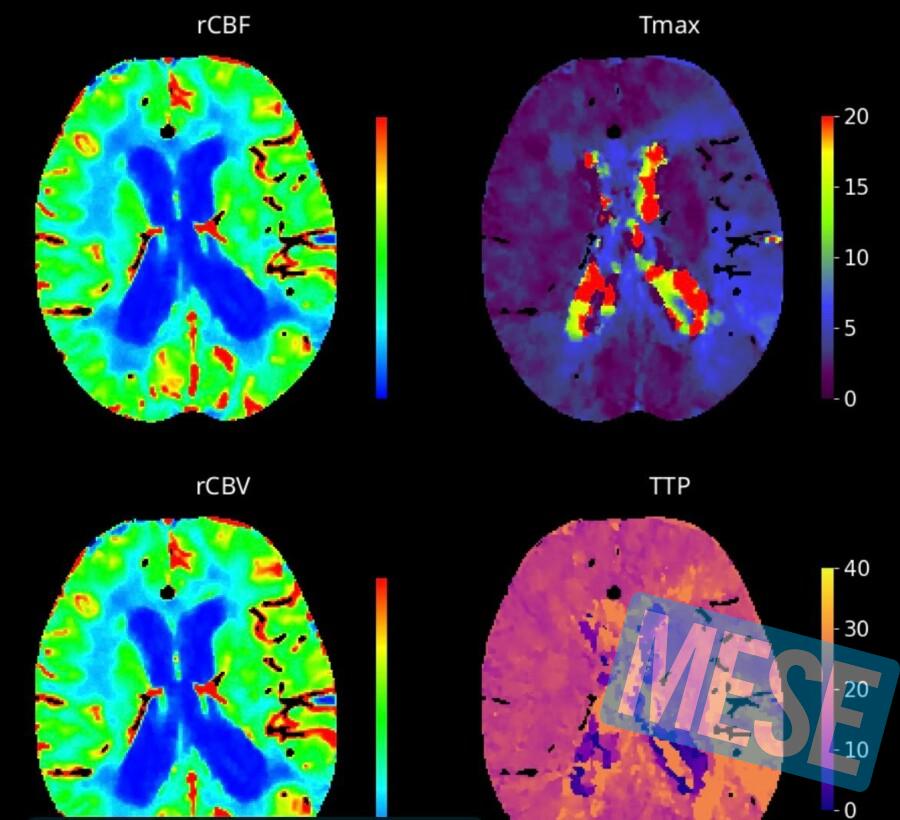

Tutti e otto gli ospedali aziendali della rete sono stati dotati di sistemi di neuroimaging avanzato. Ciò significa che le radiologie dei rispettivi Pronto Soccorso sono oggi in grado di eseguire in urgenza la TC perfusionale, una tecnica neuroradiologica evoluta che permette di valutare con maggiore accuratezza la presenza di tessuto cerebrale recuperabile. Questo approccio consente in casi selezionati di ampliare la cosiddetta finestra terapeutica, cioè l’intervallo di tempo entro il quale è possibile trattare efficacemente un paziente dopo l’insorgenza dell’ictus. Per la trombolisi, che consiste nella somministrazione endovenosa di un farmaco in grado di sciogliere il trombo, il limite temporale può essere esteso dalle tradizionali 4 ore e mezza fino a 9 ore e in futuro anche oltre, e può essere effettuata in molti casi anche quando l’orario di insorgenza non è noto, come nell’ictus al risveglio.

L’impiego di questo tipo di imaging permette, quindi, di ampliare la finestra di trattamento rispetto ai sistemi diagnostici di base, offrendo a un numero maggiore di pazienti la possibilità di accedere alle terapie più appropriate. La disponibilità di un imaging avanzato si traduce così, in un aumento dei pazienti eleggibili al trattamento, in una maggiore probabilità di preservare tessuto cerebrale vitale e di aumentare il numero di persone sottratte alla disabilità. Quantomeno nel riuscire a ridurla.

“Le ricadute sono state fin da subito molto positive, sia sulla tempestività diagnostica sia sulla qualità complessiva del percorso assistenziale del paziente con ictus ischemico – sottolinea Angela Konze, direttore della SOSD di Neuroradiologia e della SOC Radiologia del presidio ospedaliero di Santa Maria Nuova, da anni impegnata a raggiungere e a diffondere l’eccellenza nella cura dell’ictus – La TC perfusionale consente di individuare il tessuto cerebrale potenzialmente recuperabile“.